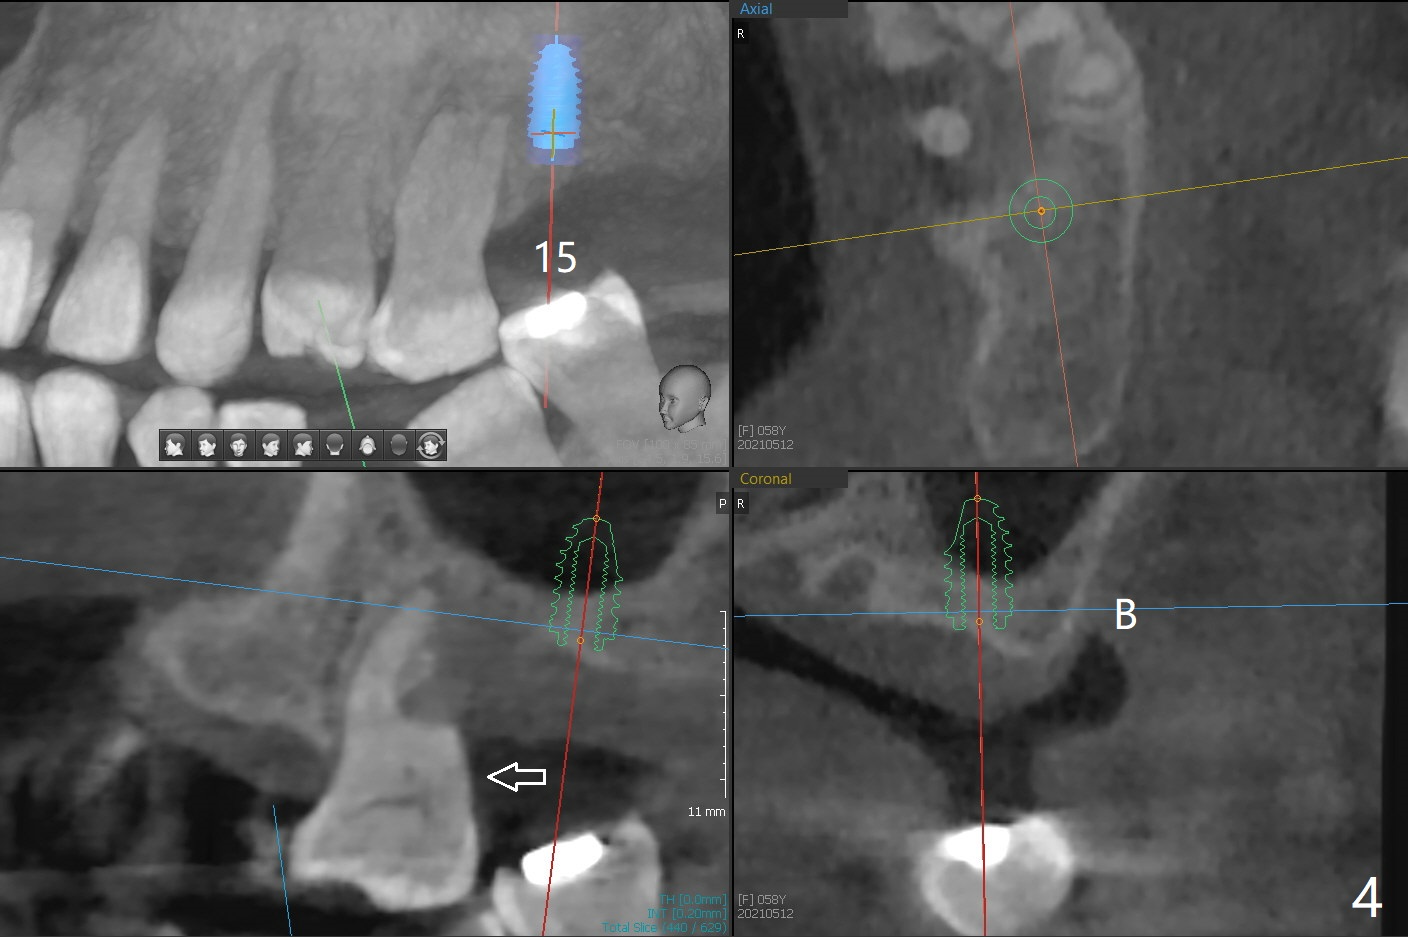

A 58-year-old woman with several restoration agrees to have implants at #15 and 19 (Fig.1). Since #18 tilts mesially, which needs to be trimmed, place #19 implant slightly distal, ~ .5 mm (Fig.2). As the infection at #14 is extensive (Fig.3), place #15 implant (probably 5x7.3 mm) distal, while tilts the long axis of the implant mesially (Fig.4 arrow). Also move the implant palatal with larger diameter and shortened length. Forget about the implant #15 if it is difficult or impossible to change.